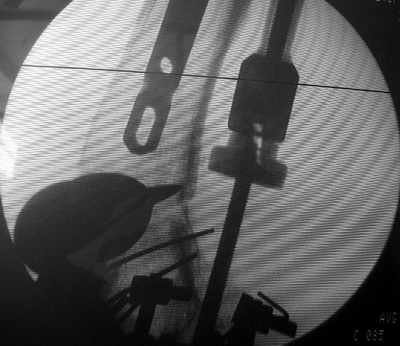

В итоге сделали антеградный остеосинтез. В дистракторе свежий перелом вправился сразу, а вот старый - оставил проблему, дистальный отлмомк остался все равно кзади. И гвоздь бы прошел кпереди от него, а ретроградный - перфорировал бы передний кортекс. Так что пришлось еще сделать чрескожную остеотомию через перелом, чтобы малость мобилизовать дистальный отломок. Снимки в прилжении.

The "idea" was an emergency appeared when the nail tip proceeded to the fracture level and became targeting anteriorly to the distal fragment.

The osteotomy was perfromed trough the fracture site. See the image.